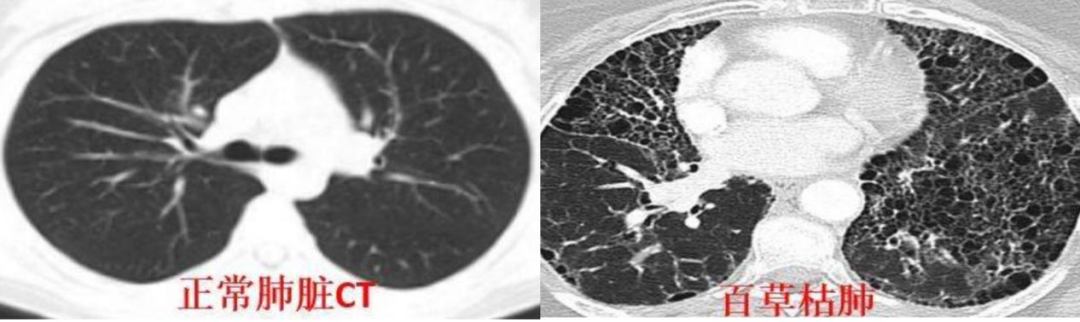

百草枯的靶器官是肺。这位医生说,肝、肾等损伤都是相对可逆的,只有肺纤维化不行。“中毒患者的肺就像‘丝瓜瓢’,满目疮痍,靠着生命维持系统能延续生命,但机器一撤,很多人立马就不行了。”